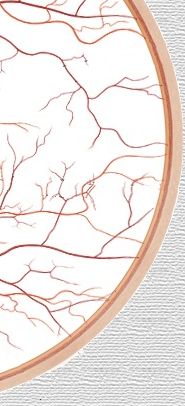

a.

retinal temporal superior |

v.

arteriola

macular superior |

vénula

retinal temporal inferior |

retinal nasal inferior |

retinal nasal superior |